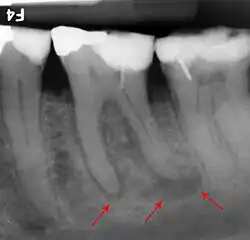

Die röntgenopaken Füllungen der Zähne erscheinen im Röntgennegativ weiß, weil die Röntgenstrahlen den Zahnfilm nicht geschwärzt haben. Die periapikale Ostitis (Pfeile) erscheint dunkel, weil durch die Osteolyse die Strahlendurchlässigkeit des Knochens erhöht wurde. Im Positiv wären die dunklen Stellen hell, weshalb man von einer Aufhellung spricht.

Röntgenopake Wurzelkanalfüllungen

In der Zahnmedizin ist die Ausprägung der Röntgenopazität ein fester Bestandteil der Diagnostik und Behandlungskontrolle. Im Vergleich zu einer 1 mm dicken Aluminiumschicht (100 %) ist Dentin 118 % und Schmelz 215 % röntgenopak. Zur Beurteilung der Dichtigkeit von Zahnfüllungen sollten diese eine Röntgenopazität von 200 % aufweisen. Glasionomerzemente besitzen eine Röntgenopazität von 200–250 %, Komposite von 250–350 %.[4] Aluminium-Silikatgläser weisen in der Regel keine genügende Radioopazität auf. Das Einfügen von geeigneten Elementen in das Aluminiumsilikatglas, beispielsweise in Form eines Austausches von Calcium in der Glaskomposition durch Barium oder Strontium, stellt diese her.[5] Die radiologische Darstellung kariöser Läsionen beruht auf der Visualisierung kariöser Läsionen über die Abnahme der Radioopazität der erkrankten Zahnhartsubstanzen, die durch den Verlust an Mineralien hervorgerufen wird.[6]